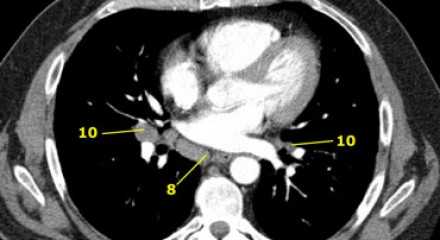

8. Параэзофагеальные лимфатические узлы

Эти лимфатические узлы ниже подкаринальных лимфатических узлов и распространяются каудальнее до диафрагмы. На изображении слева ниже уровня карины справа от пищевода обозначен лимфатический узел 8 группы.

На ПЭТ изображении слева показано накопление 18Р-дезоксиглюкозы в узле 8 группы. На соответствующем КТ изображении видно что данный лимфатический узел (голубая стрелка) не увеличен. Вероятность того что в имеется метастатическое поражение данного узла чрезвычайно высока, поскольку специфичность ПЭТ выше чем измерение размеров лимфатических узлов.

10. лимфатические узлы корня легкого

Лимфатические узлы корня расположены проксимальнее долевых узлов, но дистальнее медиастинальной дупликатуры и узлов промежуточного бронха справа.

Все лимфатические узлы 10-14 групп являются N1 узлами, так как они находятся вне средостения.